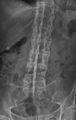

"Bamboo spine" develops when the outer fibers of the fibrous ring (anulus fibrosus disci intervertebralis) of the intervertebral discs ossify, which results in the formation of marginal syndesmophytes between adjoining vertebrae.

The earliest changes demonstrable by plain X-ray shows erosions and sclerosis in sacroiliac joints. Progression of the erosions leads to widening of the joint space and bony sclerosis. X-ray spine can reveal squaring of vertebrae with bony spur formation called syndesmophyte. This causes the bamboo spine appearance. A drawback of X-ray diagnosis is the signs and symptoms of AS have usually been established as long as 7–10 years prior to X-ray-evident changes occurring on a plain film X-ray, which means a delay of as long as 10 years before adequate therapies can be introduced.[25]

X-ray showing bamboo spine in a person with ankylosing spondylitis